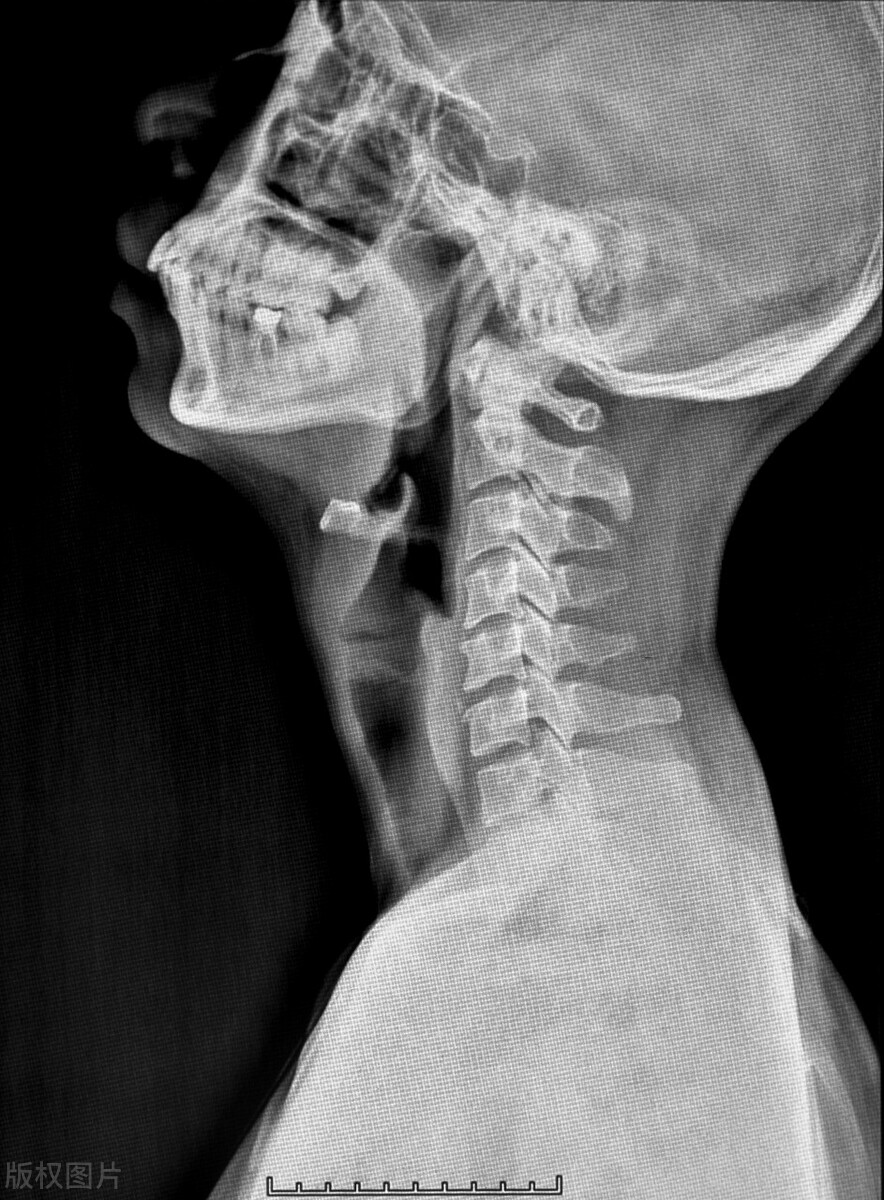

半个月前来问诊,通过核磁检查,显示患者颈椎间盘突出压迫神经。